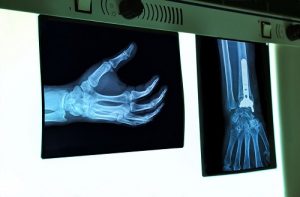

Что касается диагностических мероприятий, то основным видом исследований при болезни Олье является рентгенография. С помощью этого метода диагностики можно получить исчерпывающую информацию о характере и степени поражения костей. Современные аппараты для проведения рентгенологического исследования, которыми оснащены клиники Израиля, позволяют также определить стадию заболевания и распространенность патологического процесса в костной системе. Помимо рентгенографии, также проводят и компьютерную томографию, которая позволяет получить послойное изображение твердых и мягких тканей.